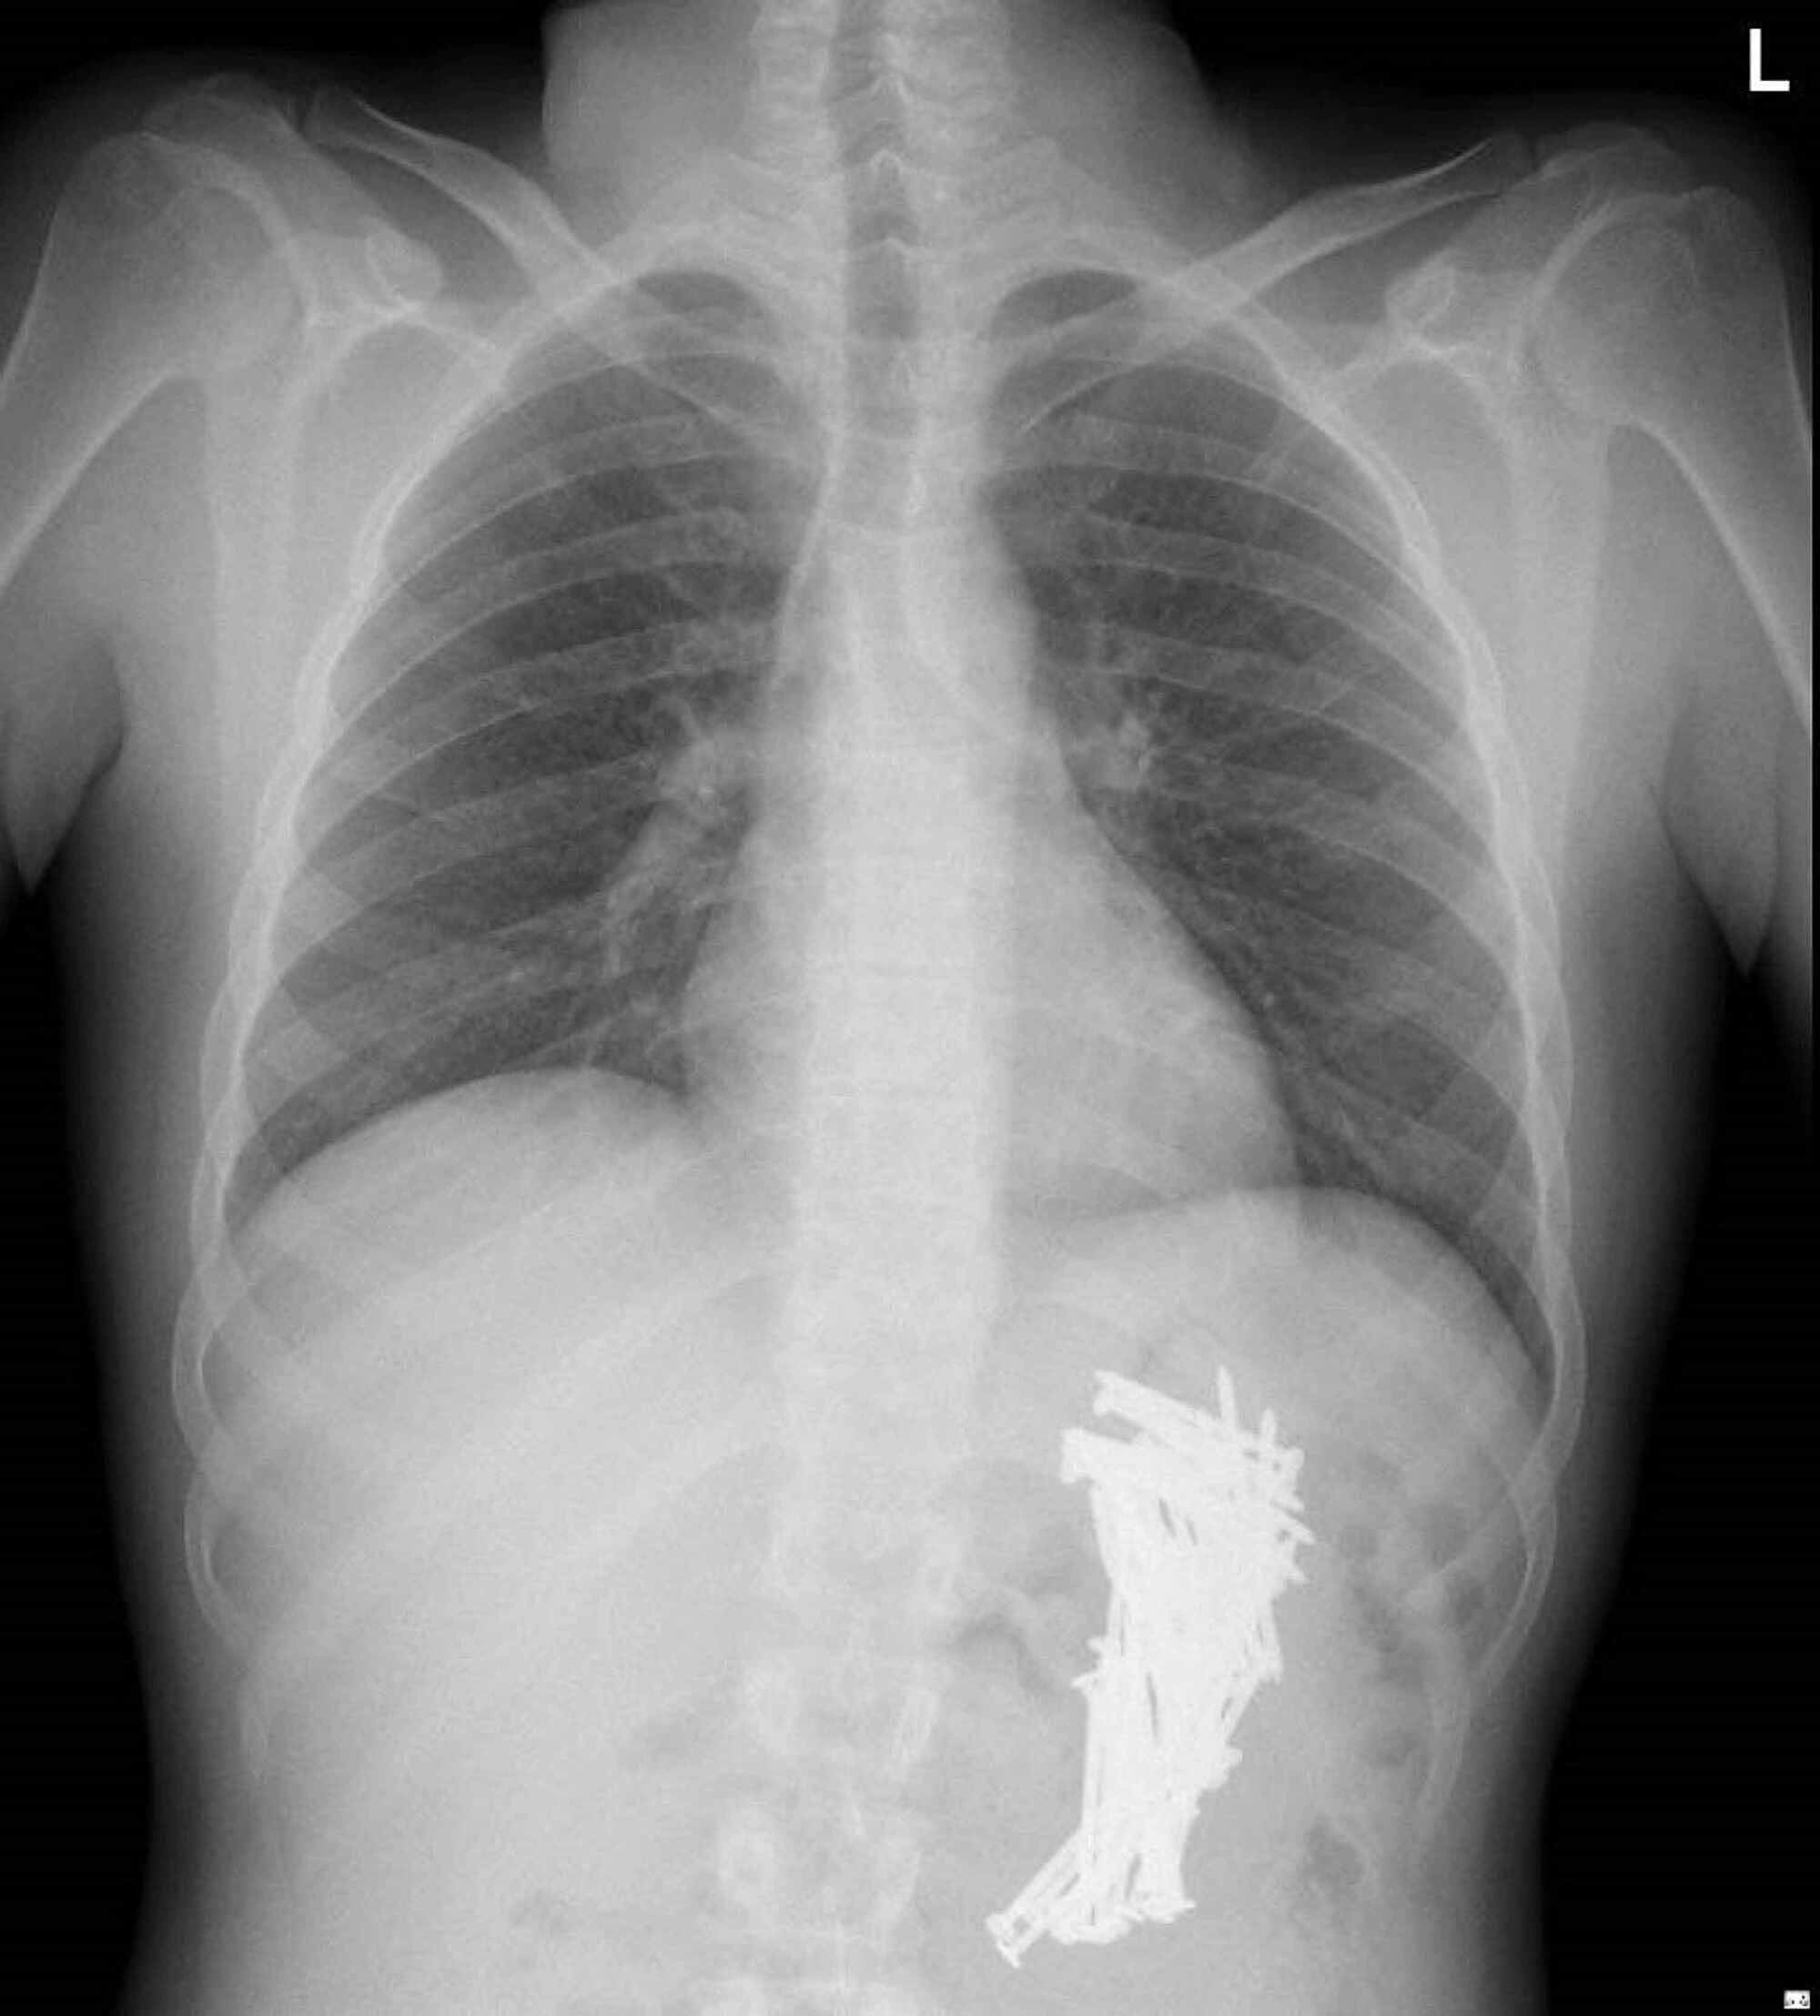

From www.cureus.com

Cureus Surgical Management of Massive Metal Bezoar Removal Of Gastric Bezoar Cpt The prevalence of a concurrent gastric bezoar is 20%. In the presence of an intestinal bezoar discovered at laparotomy. This chapter describes the surgical procedure for the removal of gastric bezoar as performed by the following approaches:. Several factors favor their formation, 1,2 and the clinical presentation may vary, including dyspepsia, anorexia, vomiting, weight loss, abdominal pain, and sometimes intestinal.. Removal Of Gastric Bezoar Cpt.